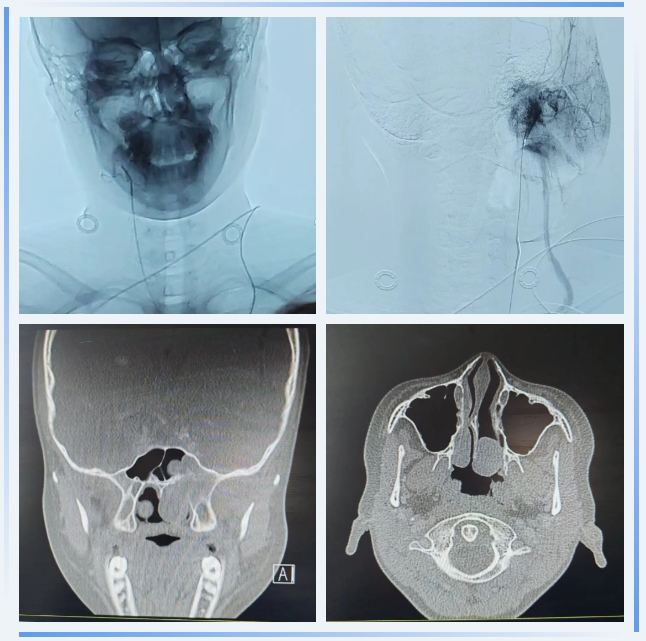

患者男,14岁,因"左侧持续性鼻塞1年"于2025年2月17日入院。鼻部CT三维重建显示:左侧鼻腔后部占位性病变,侵袭鼻咽腔及左侧翼腭窝,伴蝶骨翼突骨质破坏,高度怀疑鼻咽纤维血管瘤。肿瘤毗邻颈内动脉及颅底重要神经,手术风险极高。

1. 介入团队精准控血:2月24日,介入科吴军主任团队通过数字减影血管造影(DSA)锁定肿瘤供血动脉,成功实施超选择性血管栓塞术,将术中出血风险降低,预防术中及术后出血;2. 麻醉团队全程护航:采用控制性降压技术,维持术中平均动脉压在90mmHg左右,进一步减少出血量。3. 重症医学科团队严密监测:患者术后转ICU,严密监测生命体征、精准护理,确保患者得到全方位的照护。